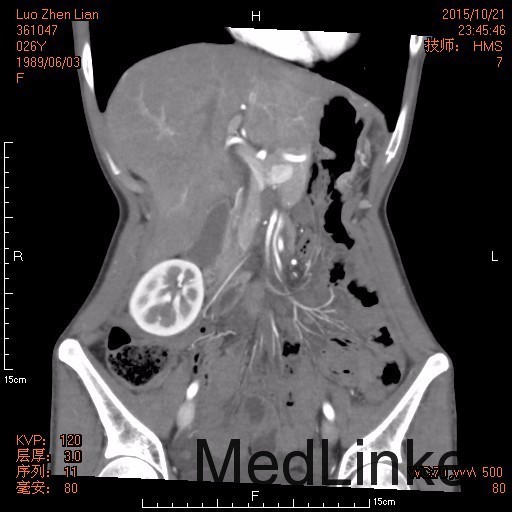

26岁女性患者,13小时前进食大枣后出现腹痛,较为剧烈,左侧腹部为主,5小时前至我院急诊,行腹部CT考虑肠系膜扭转,由急诊收入我科。3年前因胃溃疡出血行胃大部切除术,一月前行内镜下胃息肉切除术。

查体: 患者呈急性痛苦面容,被动屈曲卧位,查体不甚合作,左下腹可见包块样隆起,肠鸣音微弱,局部板状腹、压痛、反跳痛明显,肛门指检未见明显异常。 辅查: 腹部增强CT :1.考虑肠系膜扭转,并肠系膜少许渗出,肠系膜区多发肿大淋巴结。 2.肝脏增大,右肾下移。 3.盆腔少量积液。

诊断:1.肠系膜扭转 2.胃大部切除术后 治疗:完善术前检查,急诊行剖腹探查+行肠系膜旋转复位 ,术后恢复良好,暂无手术相关并发症出现。